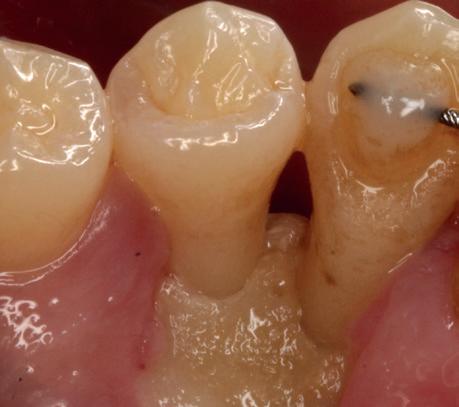

Casus

In deze casus is extractie van de 37 geïndiceerd in verband met een fistel en restpockets, zoals zichtbaar op de röntgenfoto’s (afbeelding 1). Duidelijk te zien is de forse peri-apicale ontsteking en het botverlies bij de 37, dat zowel richting buccaal als linguaal doorloopt. De 37 wordt atraumatisch verwijderd. Er is aan de linguale zijde veel bot verloren en er is sprake van een perforatie aan de buccale zijde.

Er wordt besloten om botmateriaal te plaatsen in de extractie-alveole. Vervolgens wordt het afgesloten met een titanium versterkt d-PTFE membraan (afbeelding 2). Na vier weken wordt het membraan verwijderd.

Zes maanden na extractie wordt het implantaat 37 geplaatst. Er is sprake van een goede genezing en de processushoogte en -breedte zijn behouden en opgebouwd. Ook is er zichtbaar gekeratiniseerd weefsel

1 2 Ridge preservation met d-PTFE membranen 35

gewonnen. De wond kan na het plaatsen van een healing abutment primair gesloten worden (Afbeelding 3a-3d).

In afbeeldingen 4a-c is het resultaat drie maanden na het plaatsen van het implantaat te zien. De genezing is volledig en de verwijzer kan de suprastructuur vervaardigen (afbeelding 4a-4c).